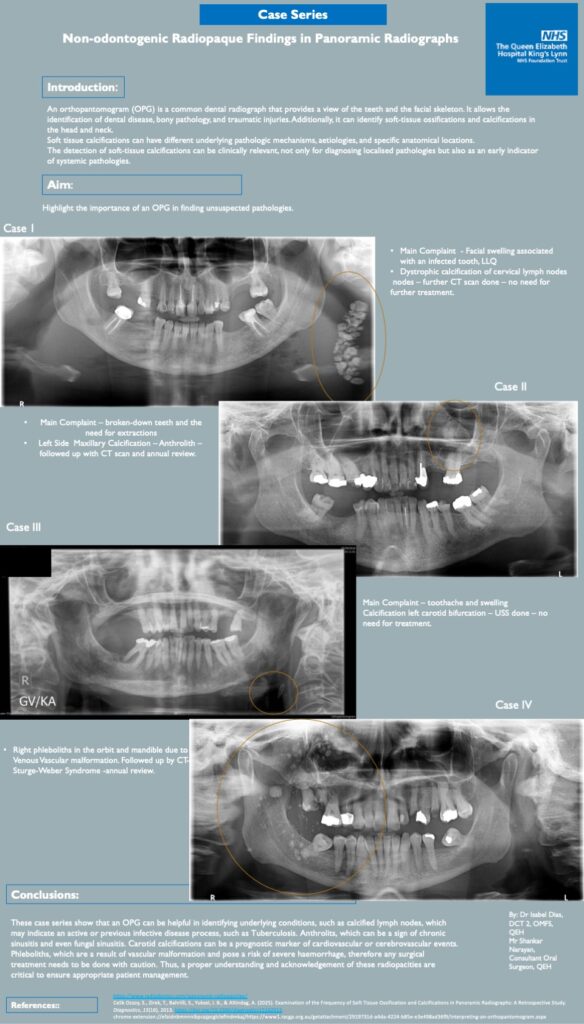

Non-odontogenic Radiopaque Findings in Panoramic Radiographs.